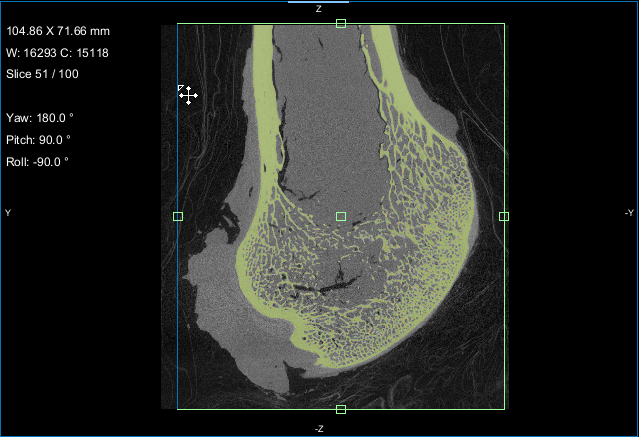

This Bone Analysis tutorial provides step-by-step instructions for segmenting a proximal femur and for computing vector-based fields of anisotropy and scalar-based maps of volume fraction. Additional topics in this tutorial describe how to compute high-resolution maps from data sub-volumes and how to evaluate the computed maps.

Screen capture of the completed tutorial